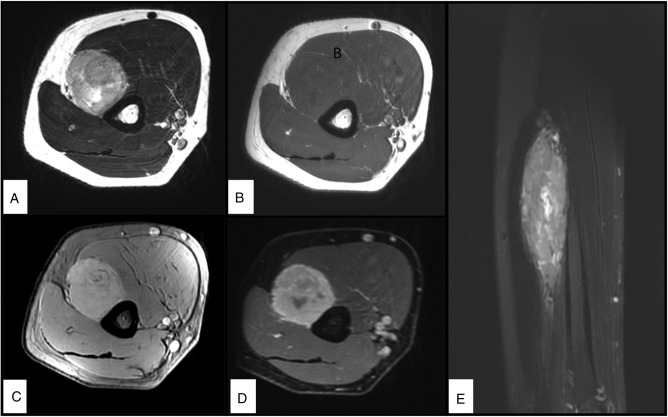

Intra-neural Ewing sarcoma is an extremely rare tumour and only a few isolated case reports exist in the literature. A 32-year-old South Asian male presented with wrist and finger drops of 3 months duration. Further evaluation with ultrasonography and magnetic resonance imaging revealed a tumour of the radial nerve in the arm. A wide excision of the tumour was performed, and the radial nerve was reconstructed with cabled nerve grafts. A diagnosis of extra-osseous Ewing sarcoma (EES) was made after histopathological evaluation using immunohistochemistry techniques. The patient subsequently received chemotherapy and after 5 months, he is disease-free and pain-free. However, there has been no motor recovery yet. Clinical findings and imaging can help and characterise the tumour, but histopathology and analysis for EWSR1 gene rearrangement are essential to confirm the diagnosis. Wide surgical excision and chemotherapy are the mainstay of managing neural EES.